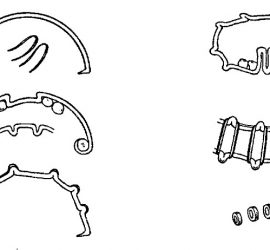

Цемент поликарбоксилатный (ТУ 64-2-275-78) выпускается Харьковским производственным объединением «Стома» (Украина). Предназначен для пломбирования молочных зубов и временных пломб, в качестве прокладок под постоянные пломбы из амальгамы, пластмассы и силикатного цемента, а также для фиксации вкладок, различных видов коронок, небольших мостовидных протезов и ортодонтических аппаратов. Поликарбоксилатный цемент выпускается в виде комплекта […]